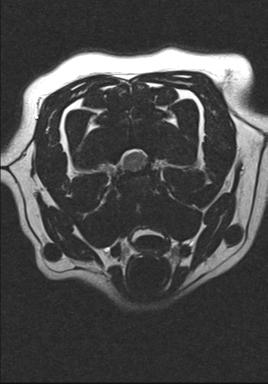

The MRI revealed Dixie to have a compression of her spinal cord, caused by the material that makes up the cushion between the bones of the spinal column spilling out and compressing the cord. The compression was in a precarious position high up in the spinal column and to address the compression would not be an easy feat.

As with any surgery the owner and vet must come to a conclusion of what is best for the patient. Dixie was in a significant amount of pain, which despite best efforts, was proving very difficult to manage with pain killers. In addition any additional leakage of disc material could leave Dixie permanently paralyzed. After a long discussion with Dixie’s owners we decided to proceed with surgery to try and remove the compression from around Dixie’s spinal cord. An intricate C2-C3 hemilaminectomy was carried out to create a window in the bone surround the spinal cord and gently tease out the offending material which was compressing the cord.  During the surgery the atmosphere in theatre was tense as there are major blood vessels which traverse this area of the spinal cord, one wrong move could cause major hemorrhage which could prove fatal!